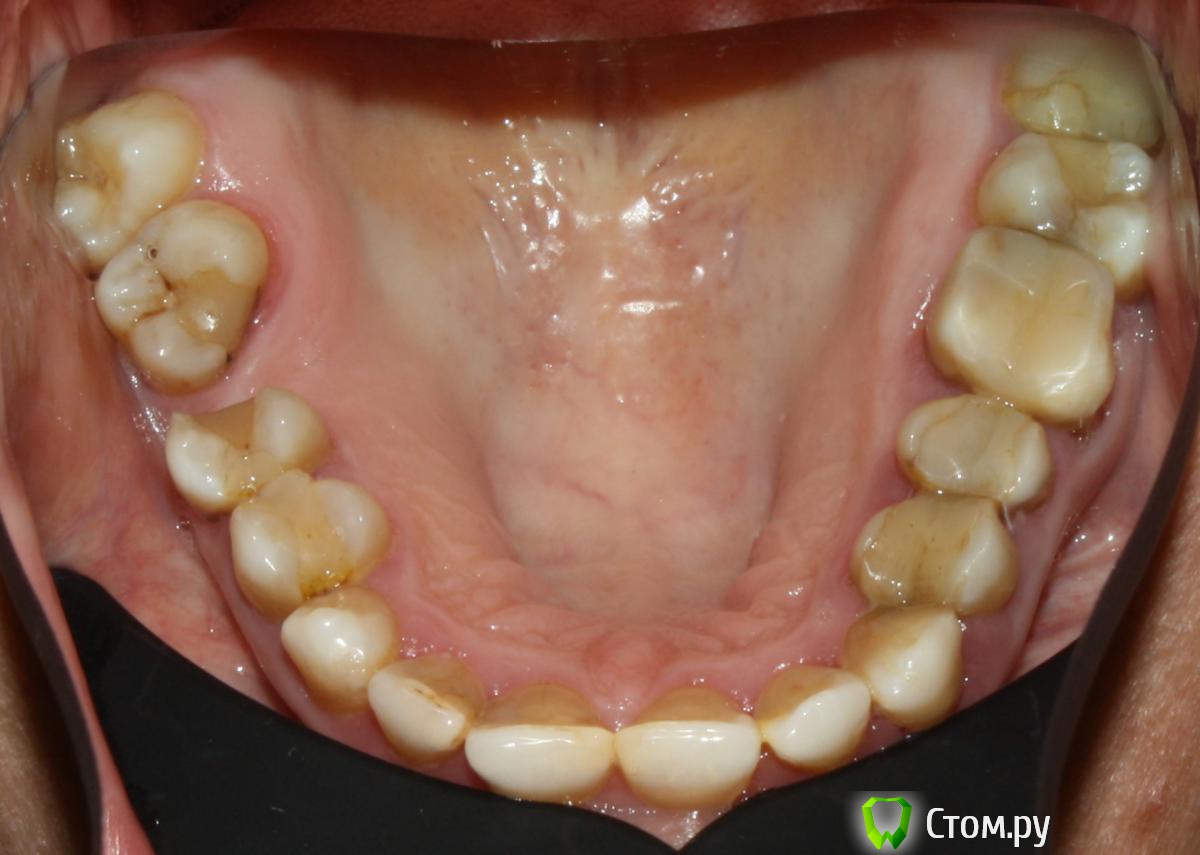

LeFor Опубликовано 18 декабря, 2013 Поделиться Опубликовано 18 декабря, 2013 насчет громоздких конструкций- смотря какой пациент... как то делал вот так...на втором снимке вверху опора на дентальный имплант- эксперимент))) 5 Ссылка на комментарий

Ibulat_1986 Опубликовано 20 декабря, 2013 Поделиться Опубликовано 20 декабря, 2013 насчет громоздких конструкций- смотря какой пациент... как то делал вот так...на втором снимке вверху опора на дентальный имплант- эксперимент)))нормально! особенно порадовал первый снимок! класс Ссылка на комментарий

LeFor Опубликовано 28 декабря, 2013 Поделиться Опубликовано 28 декабря, 2013 (изменено) Аня, всё Вы правильно понимаете, ну, во всяком случае, почти правильно В ортодонтии есть такой важный раздел, который называется - "Основы механики". Не изучив должным образом этот раздел, крайне сложно заниматься ортодонтией, да и опасно, т.к. всё будет превращаться вот в такие "эксперименты" Так вот, интрузия верхнего моляра, с точки зрения тех самых основ механики, вещь весьма проблематичная, если вести речь об истинной интрузии. Об этом и в литературе много пишут, но каждый раз кто-то, в очередной раз, пытается изобрести велосипед. С тех же позиций основ механики, можно объяснить, почему у доктора, со звучным ником LeFor, верхний моляр ротировался нёбно. Всё же довольно элементарно, если знать и помнить о таких понятиях, как центр сопротивления и момент силы. Планировать такие перемещения нужно не исходя от того, где хирургу удобно вкрутить шуруп, а именно из этих понятий - центр сопротивления и момент силы. Для справки. Результирующая сила, действующая на зуб при интрузии, должна совпадать с центром сопротивления. Это двольно сложно расчитать, но приблизительно можно. Используйте дополнительно окклюзионную нагрузку при интрузии моляров.Эх.... сейчас, какашки вытру с головы и все расскажу... история такая... пациент 56 лет, работает "на северах" с непредсказуемым сроком вахты(и непредсказуемым отношением к гигиене- это видно на снимке), необходимость в "изобретении велосипеда" возникла после троекратной потери винта с вестибулярной стороны(гайморова пазуха занимает максимум объема вч, и скулового отростка вч в том числе + возможно гигиеническое состояние помогало), при этом небный винт был установлен достаточно успешно. Так вот, данный "велосипед" был стабилизирован именно небным винтом, до того момента пока пациент не порвал эластик с небной стороны... в таком состоянии он благополучно просидел в тайге 2 месяца, от чего и получился такой "предварительный" результат...... на котором я сознательно не стал заострять внимание, и упреждающе назвал "экспериментом"... НО "созвучный" доктор Skip так ослеп от своего теоретичесого эго, что забыл об элементарных проблемах житейской практики, и в очередной раз сорвался с цепи завидев лишь тень намека на такую возможность... и глазом не моргнул, и не стал "опускаться" до уровня элементарных "деонтологических" вопросов, типа: док, а что там за хрень на верхнем зубе? его кажись повело? ответ: да там такой вот косяк вышел, исправим... но нет! созвучный Скип- ясновидящий! сразу узрел корень зла в некомпетентности врача! Изменено 28 декабря, 2013 пользователем LeFor 1 Ссылка на комментарий